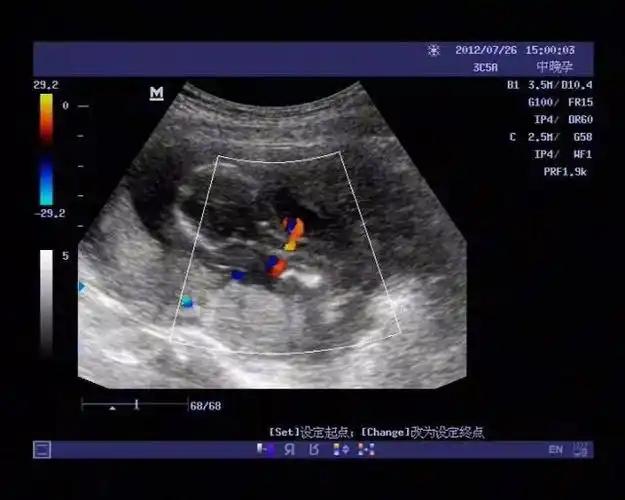

脐带绕颈怎么办,对胎儿有危险么?